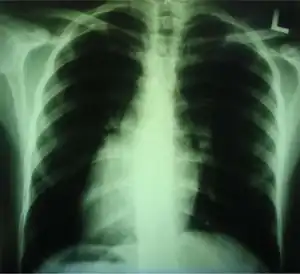

Dextrocardia (from Latin dextro, meaning "right hand side," and Greek kardia, meaning "heart") is a rare congenital condition in which the apex of the heart is located on the right side of the body, rather than the more typical placement towards the left.[1][2]

Dextrocardia situs inversus refers to the heart being a mirror image situated on the right side. For all visceral organs to be mirrored, the correct term is dextrocardia situs inversus totalis.[5][6]